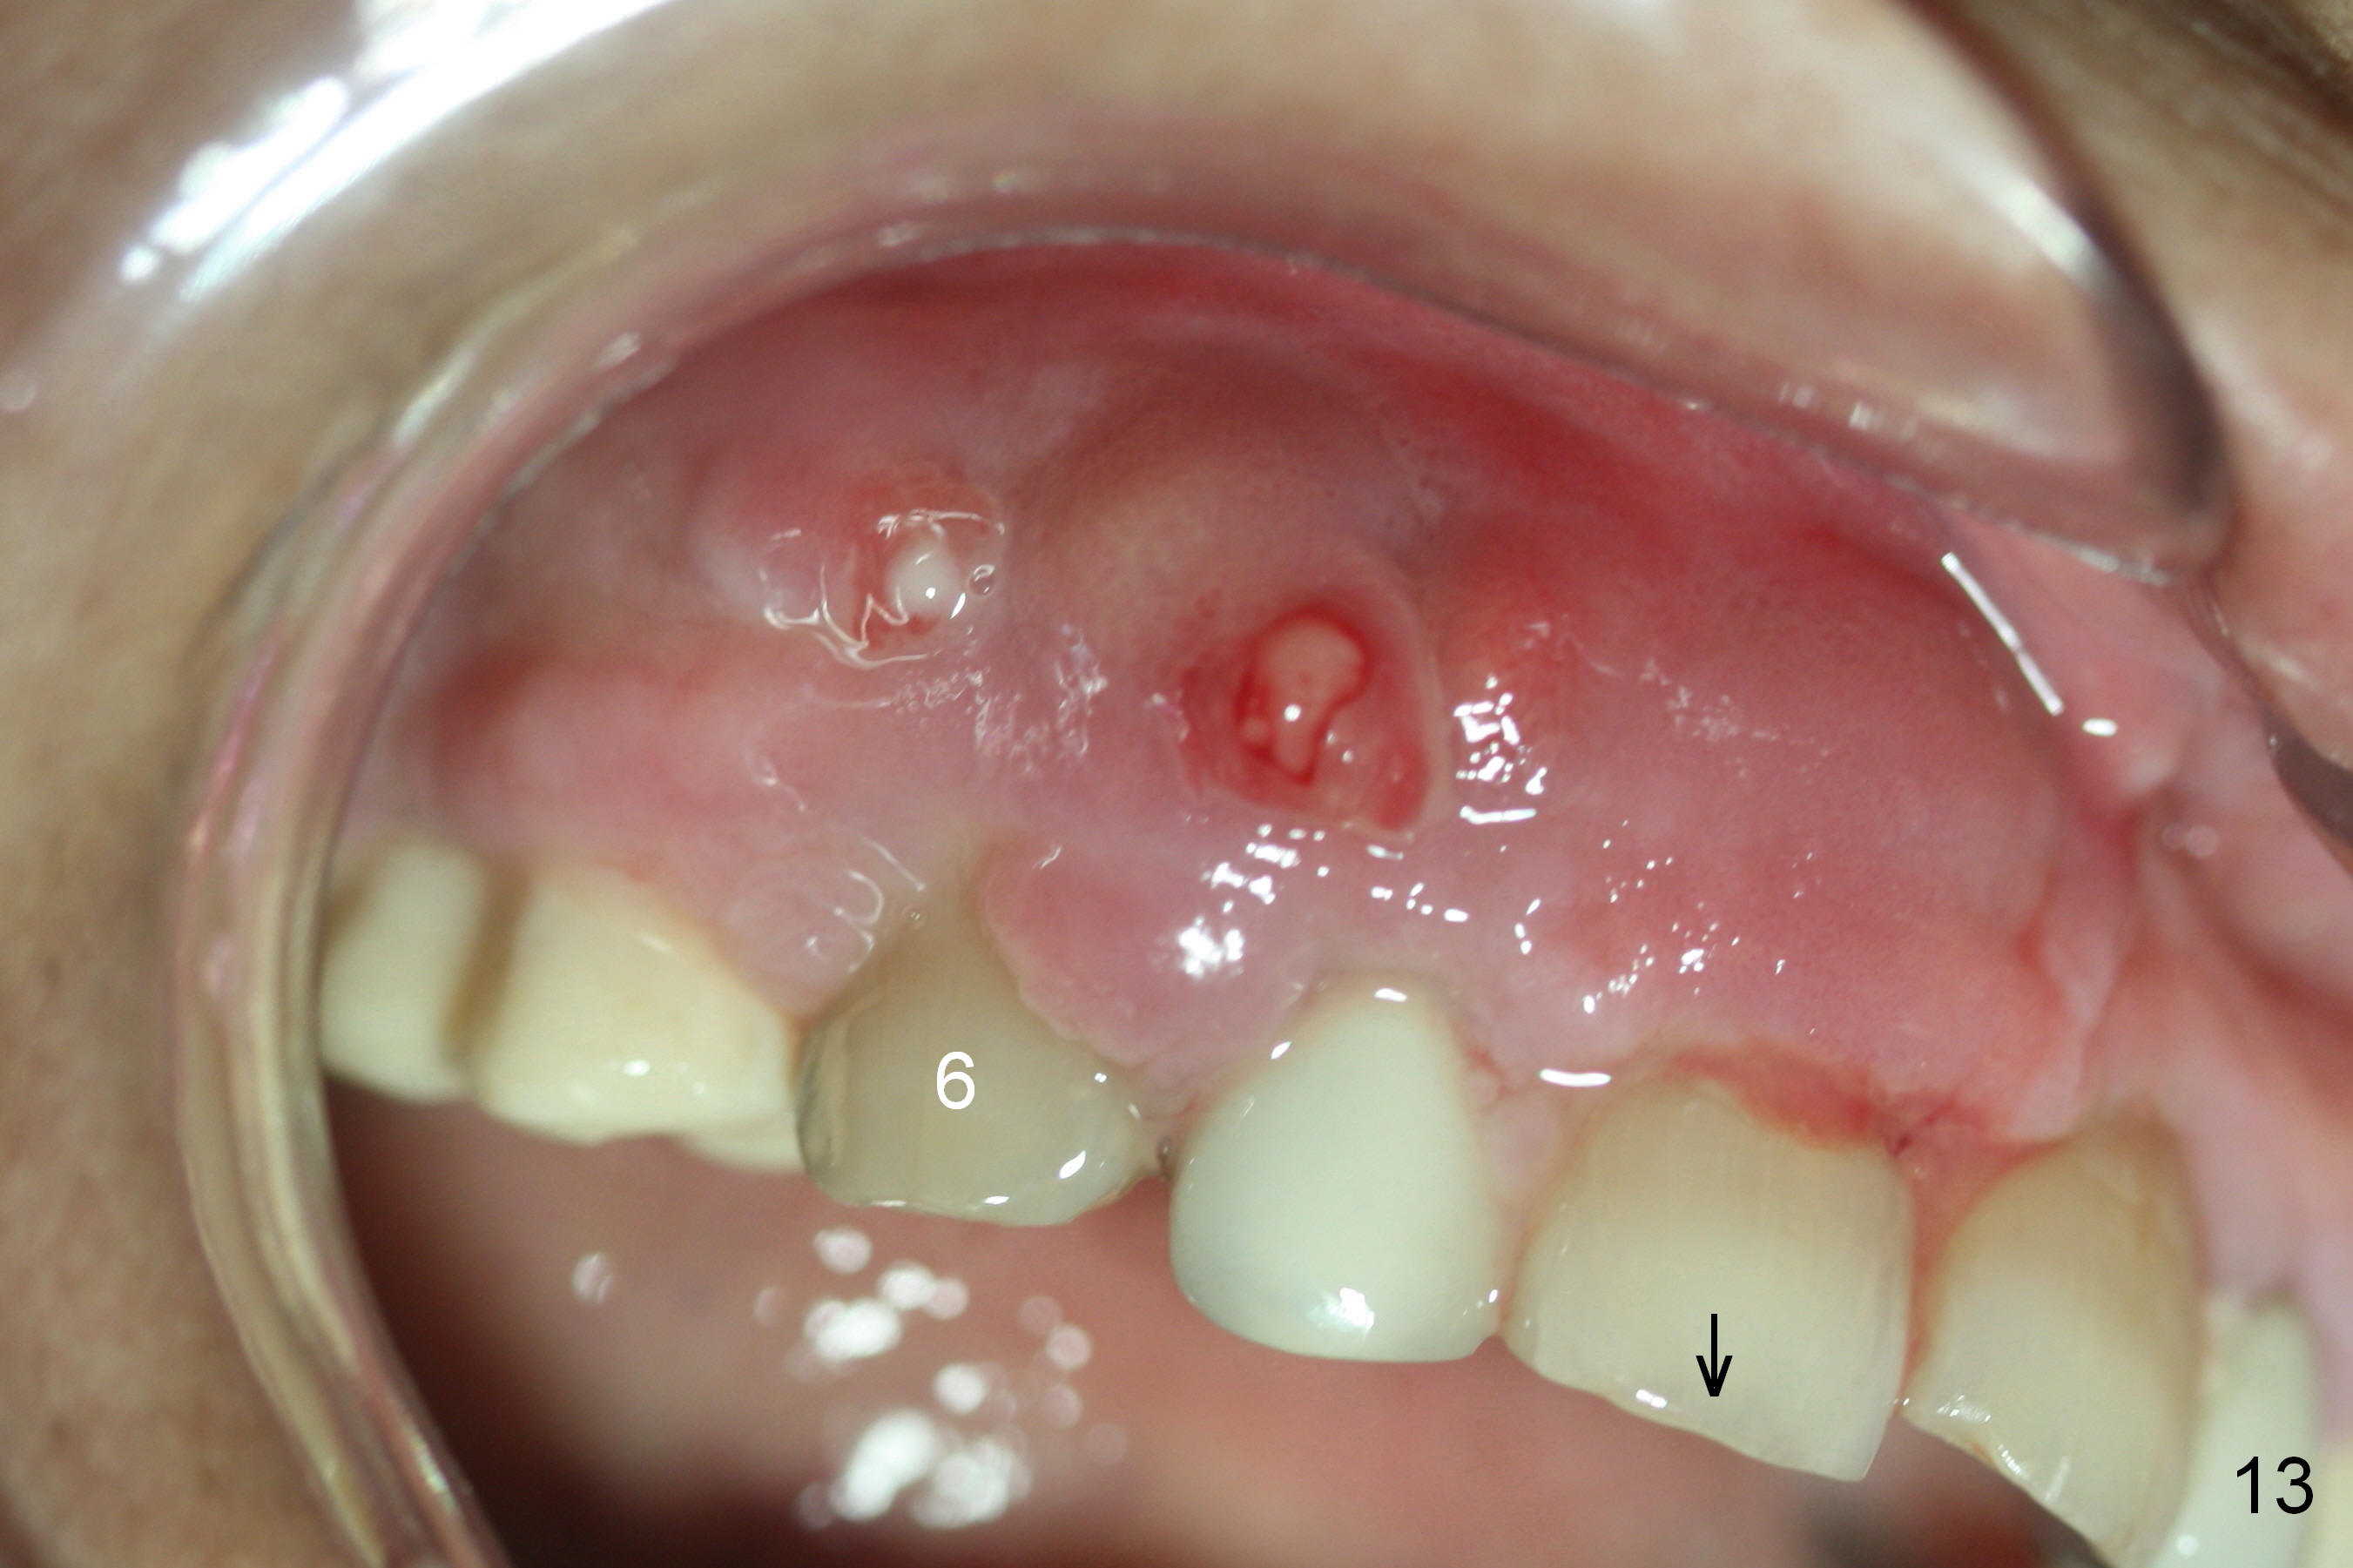

Although the patient feels better after taking Amoxicillin, the infection remains at #6-8 five weeks postop (Fig.12,13). The tooth #8 appears to be extruded with >10 mm buccal pocket. Water pik is recommended. It seems that the teeth #6-8 should be extracted and replaced with implants. Scaling & root planing should be tried first (Fig.11,12).